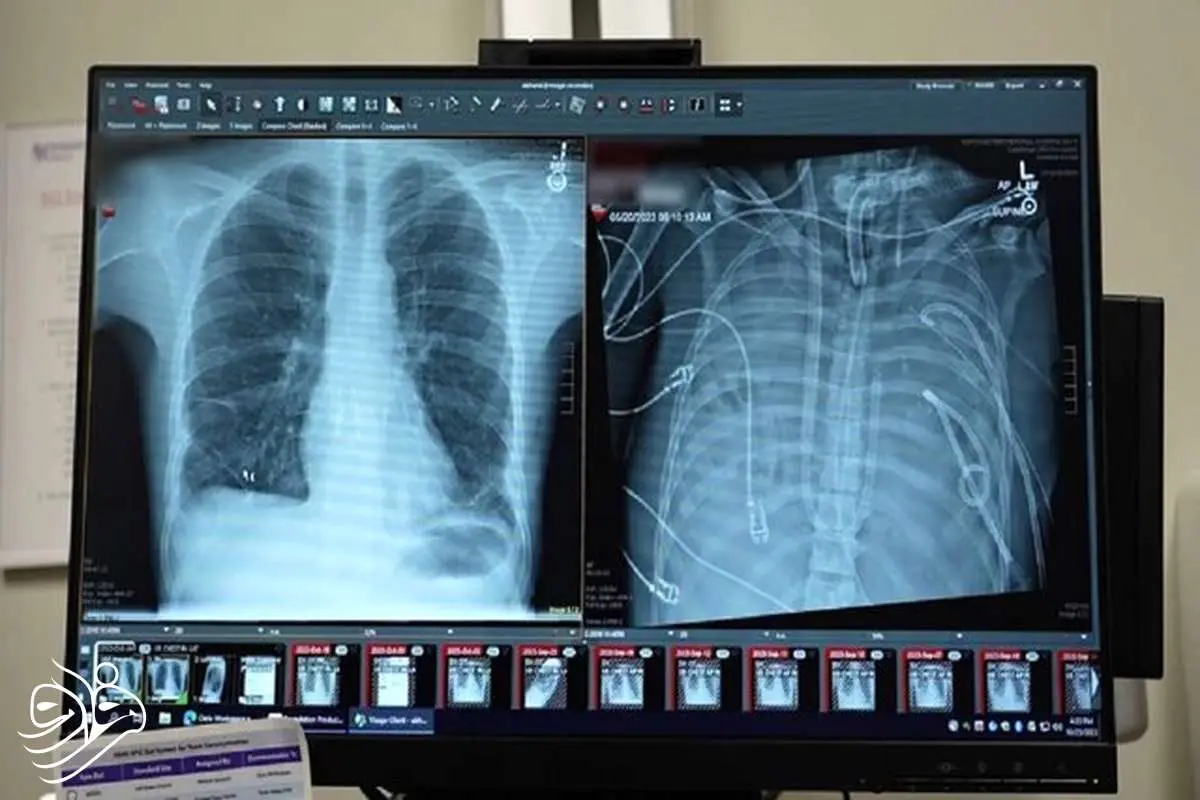

پزشکان دانشگاه نورث‌وسترن آمریکا برای نخستین بار موفق شدند مردی ۳۳ ساله را به مدت ۴۸ ساعت بدون داشتن حتی یک ریه زنده نگه دارند؛ آن هم با کمک یک سیستم ریه مصنوعی خارجی که نه‌تنها اکسیژن‌رسانی می‌کند، بلکه عملکرد طبیعی قلب را نیز حفظ می‌کند. این دستاورد می‌تواند آینده پیوند ریه را برای بیماران بدحال متحول کند.

یک مرد ۳۳ ساله بعد از اینکه گروه پزشکی، اعضای بدنش را با یک سیستم ریه مصنوعی خارجی جایگزین کردند که توسعه یافته بود تا او را زنده نگه دارند که بتواند پیوند دو ریه دریافت کند، به مدت ۴۸ ساعت بدون ریه‌هایش زنده ماند.

وضعیت تهدیدکننده حیات

قبل از قرار گرفتن روی سیستم ریه مصنوعی، این مرد دچار سندرم حاد دیسترس تنفسی شده بود که یک وضعیت اغلب تهدیدکننده حیات است که در آن ریه‌ها نمی‌توانند اکسیژن کافی جذب کنند و این مشکل توسط ویروس آنفلوانزا ایجاد شده بود. سپس او روی ونتیلاتور قرار گرفت، اما دچار عفونت مقاوم به دارو شد. این عفونت باعث شد قسمت‌هایی از ریه‌های او پر از چرک شود و او وارد شوک سپتیک شود که در این مرحله قلب و کلیه‌هایش شروع به از کار افتادن کردند.

بهارات می‌گوید: او خیلی بیمار بود، دچار ایست قلبی شد و در حال مرگ بود. از آنجا که این مرد خیلی بیمار بود که پیوند ریه دریافت کند، گروه پزشکان تصمیم گرفتند ریه‌های او را که منبع عفونت بود، بردارند.

به طور شگفت‌انگیز، مرد شروع به بهبود سریع کرد. در عرض ۴۸ ساعت، او همه داروها برای حمایت از فشار خون را کنار گذاشت، عملکرد کلیه او کاملا بازیابی شد و قلب او به طور طبیعی کار می‌کرد. در این مرحله، مرد پیوند دو ریه را دریافت کرد و سال‌ها بعد هیچ نشانه‌ای از رد عضو یا اختلال عملکرد ریه نشان نداد. اکنون تقریبا سه سال از انجام این کار گذشته است و حال بیمار واقعا خوب است.